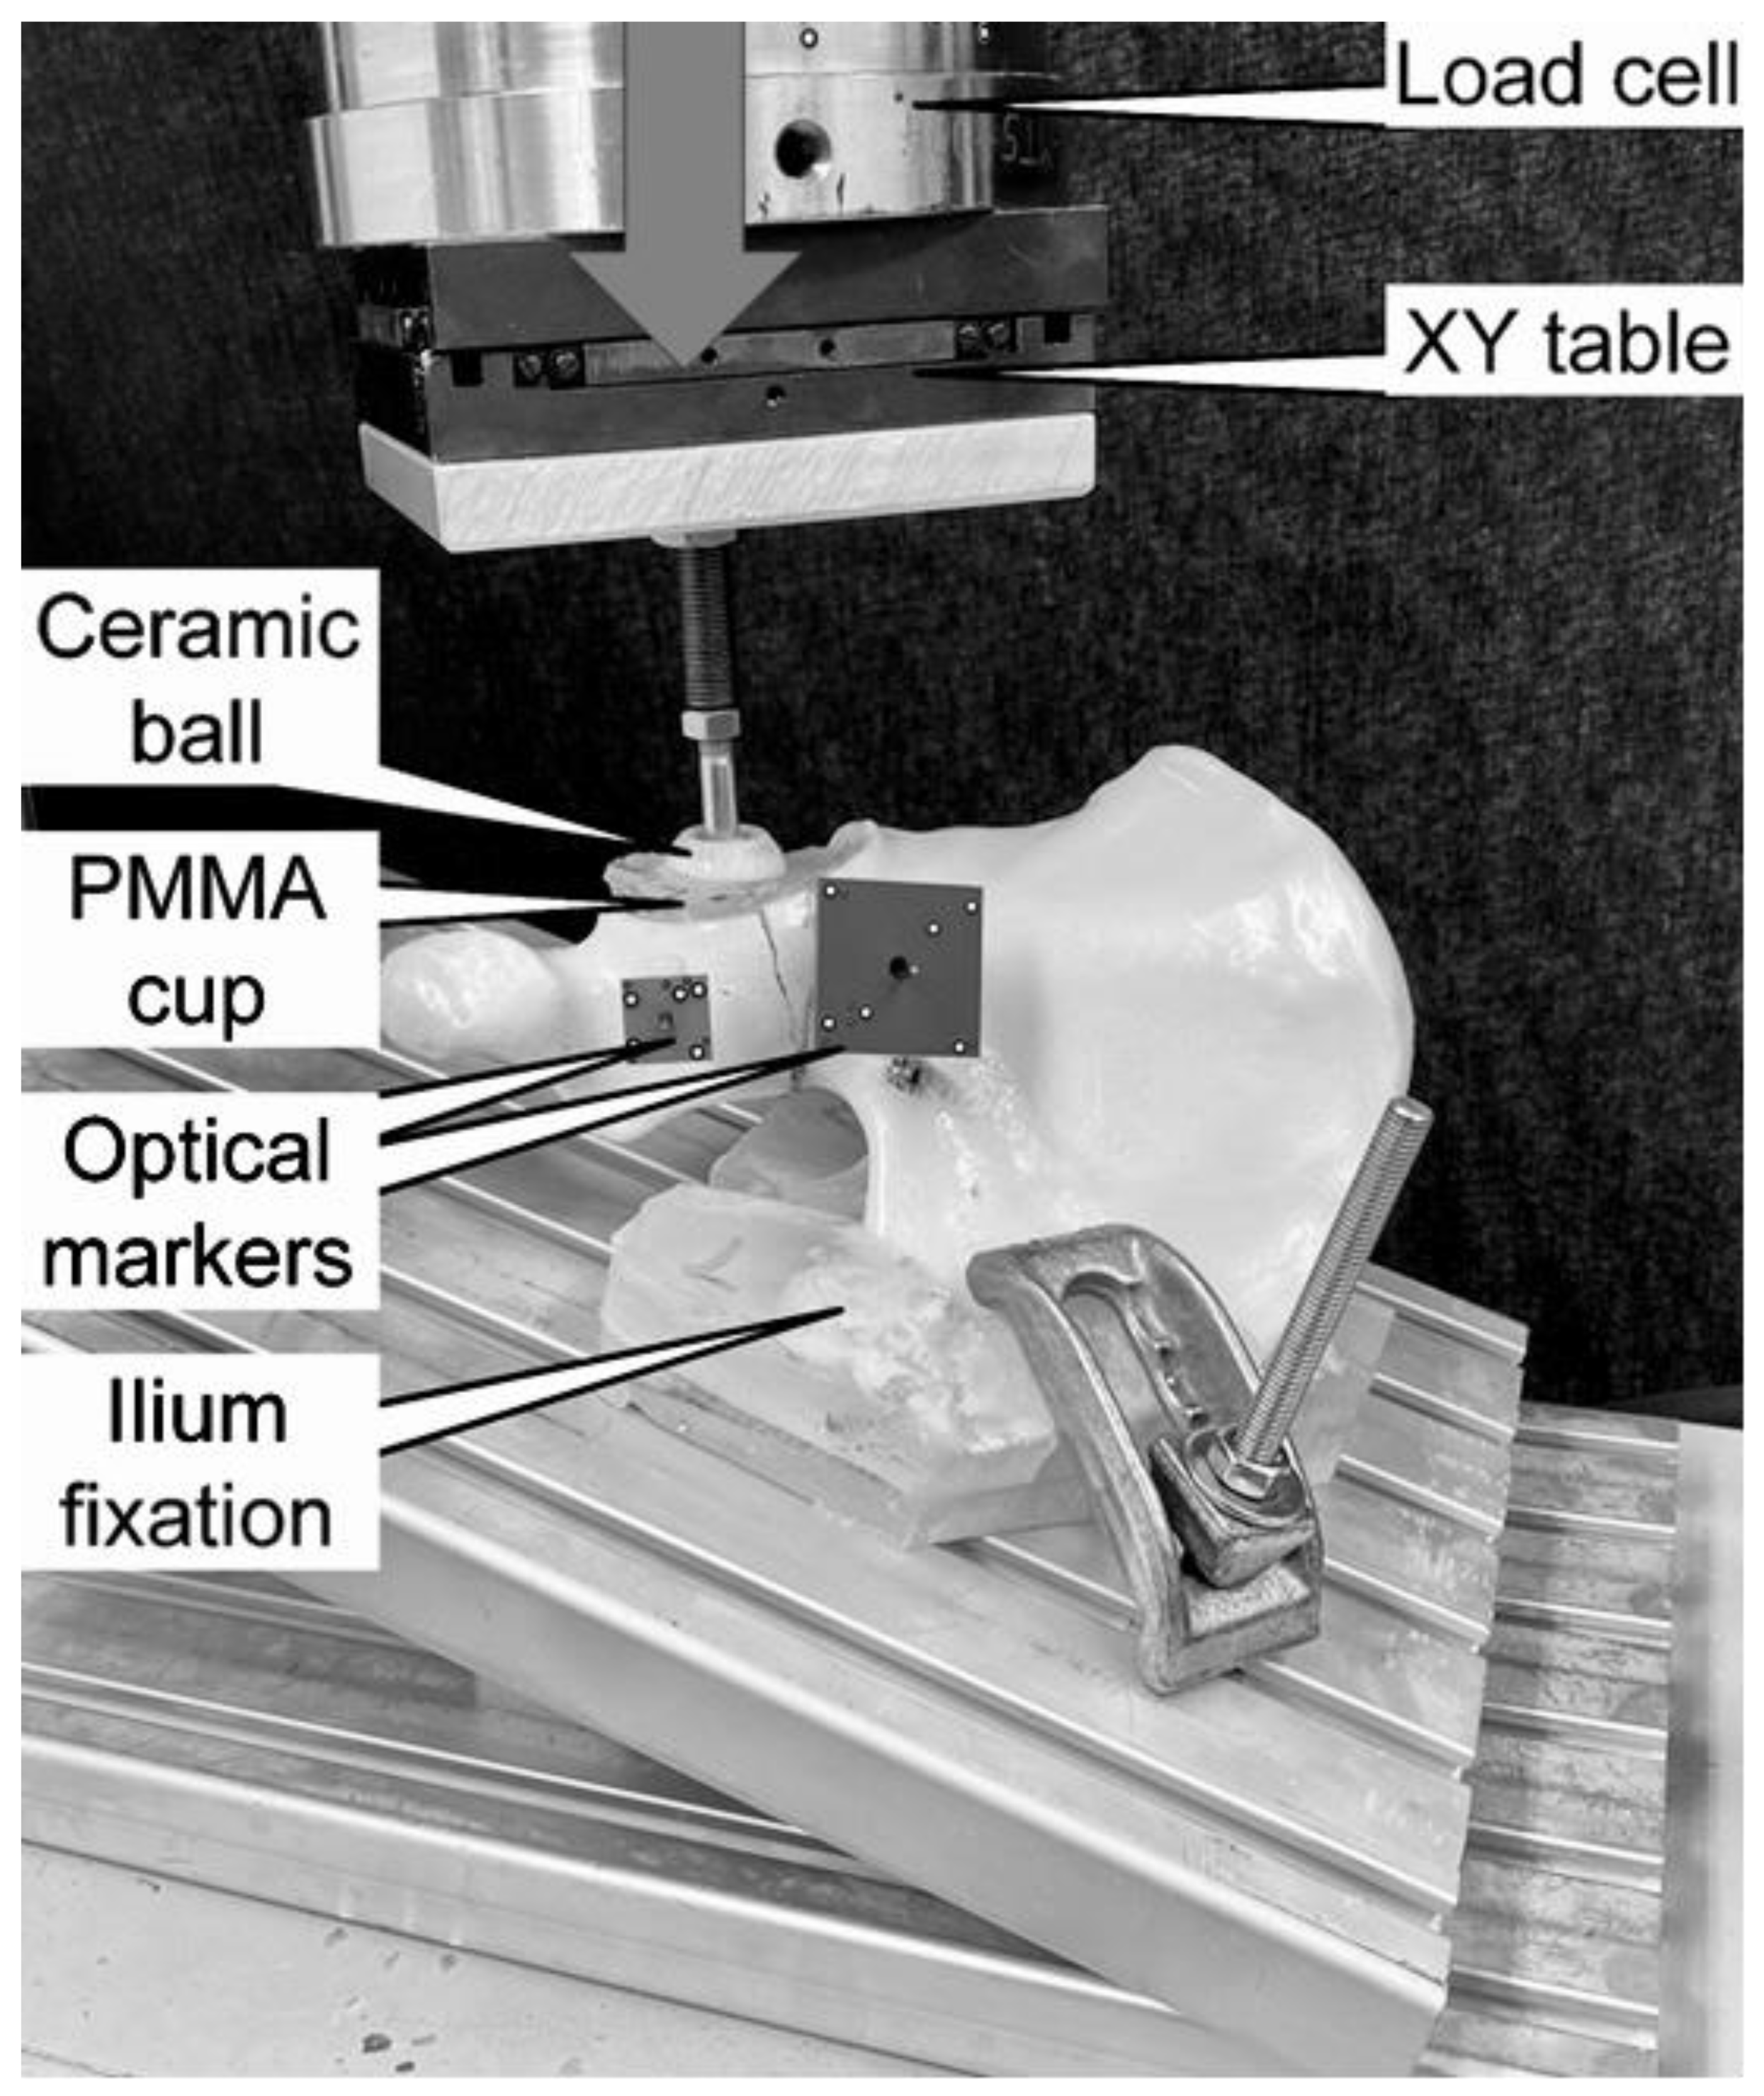

2. Materials and Methods

2.1. Biomechanical Testing